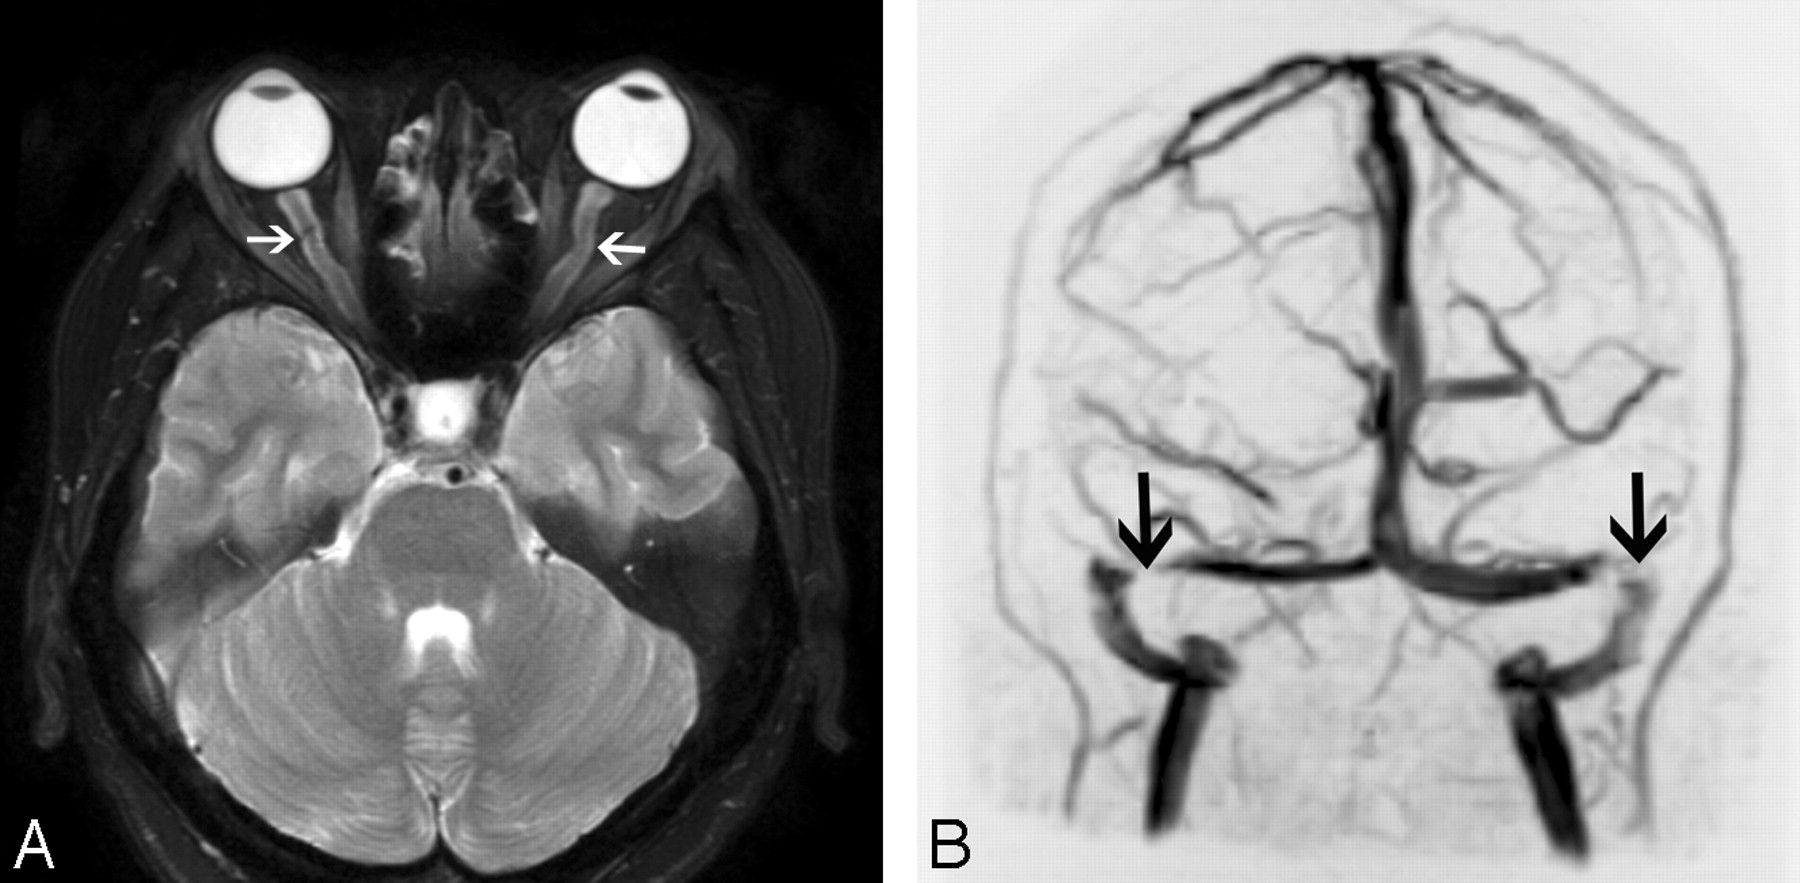

MR imaging findings of posterior globe flattening, optic nerve sheath distension, optic nerve tortuosity, pituitary deformity, and empty sella turcica are significantly associated with IIH (Fig 11A). However, cross-sectional imaging is neither sensitive nor specific for making this diagnosis. Flattening of the posterior aspect of the globe is the only sign that, if present, is suggestive of the diagnosis of IIH (specificity 100%, sensitivity 43.5%).47

Intracranial hypertension in a 30-year-old woman presenting with headaches and tinnitus. A, Axial T2-weighted image demonstrates dilation of bilateral optic nerve sheaths (arrows) and flattening of the posterior globes. B, Coronal maximum-intensity-projection image from an MR venogram also demonstrates stenoses of bilateral transverse sinuses (arrows).

Dural Sinus Stenosis.

The intracranial dural venous sinuses vary in size in different patients, and often paired sinuses, especially the transverse sinuses, are asymmetric. However, most patients have no related symptoms. If a patient has a focal stenosis of a dural venous sinus, turbulent flow may cause tinnitus.48 This abnormality can be assessed with MR imaging (Fig 11B) or CT venography. MR imaging may also show other signs of intracranial hypertension. The causal relationship of venous sinus stenosis and intracranial hypertension is controversial.49 Dilation and stent placement of the lateral venous sinuses have produced clinical improvement in some patients with IIH who had high venous sinus pressures.50